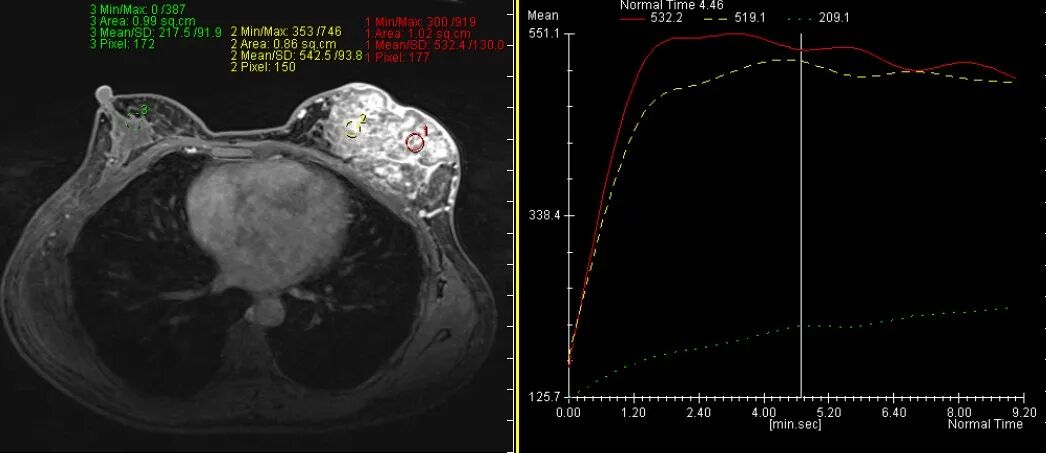

乳腺炎:包括急、慢性乳腺炎和乳腺脓肿,多见于产后哺乳期妇女,急性乳腺炎常有典型的临床症状-红、肿、热、痛;若治疗不及时可形成慢性乳腺炎或乳腺脓肿。MG 表现片状致密影,边缘模糊,患处皮肤水肿增厚,皮下脂肪层模糊;MRI-T1WI 表现为片状低信号,T2WI 高信号,信号强度不均匀,边缘模糊,皮肤水肿、增厚,增强 MRI 通常表现为轻至中度强化,且以延迟强化为主。